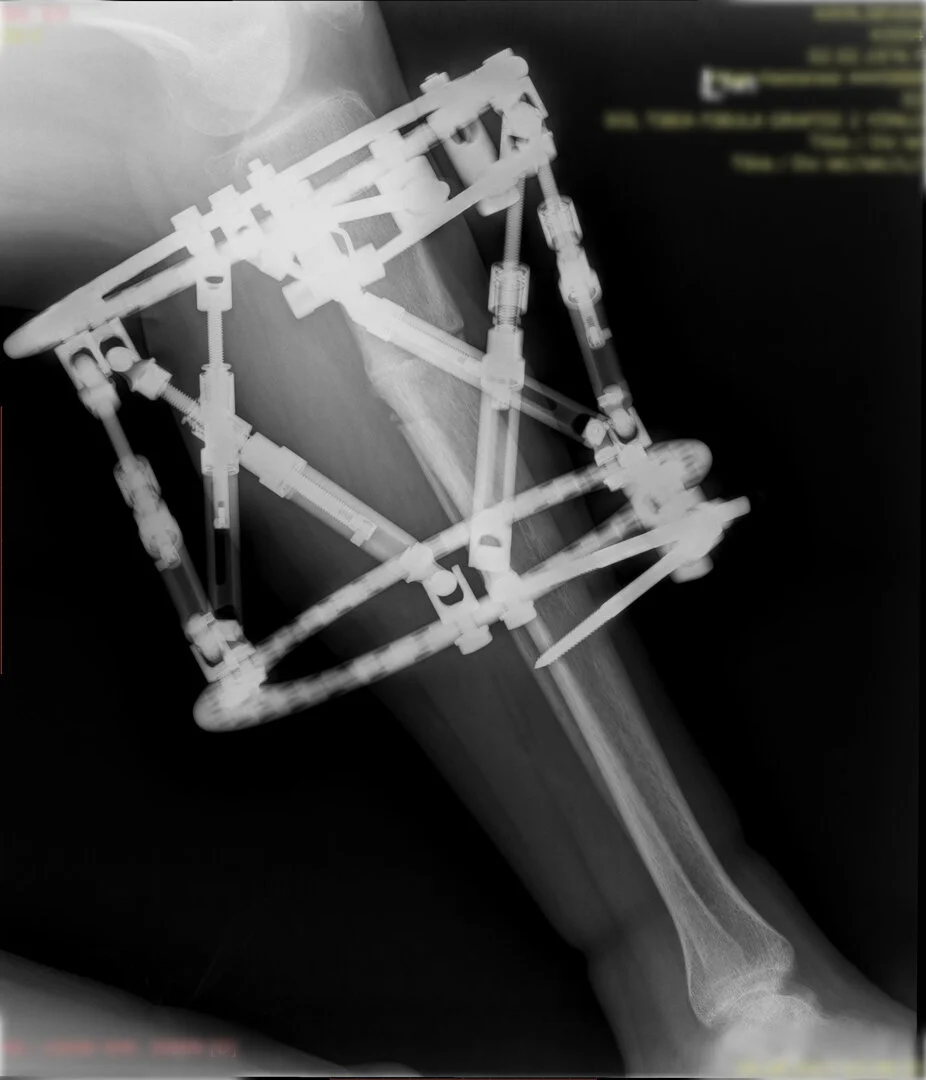

Deformitenin yeri ve miktarına bağlı olarak bilgisayar destekli sirküler eksternal fiksatör ile tedrici düzeltme yapılabilir. Bu sistemin avantajı düzeltme esnasında sistemle oynayarak yeni düzenlemeler yapmanıza izin vermesidir.

Görüntüleri büyütmek için üzerine tıklayınız.